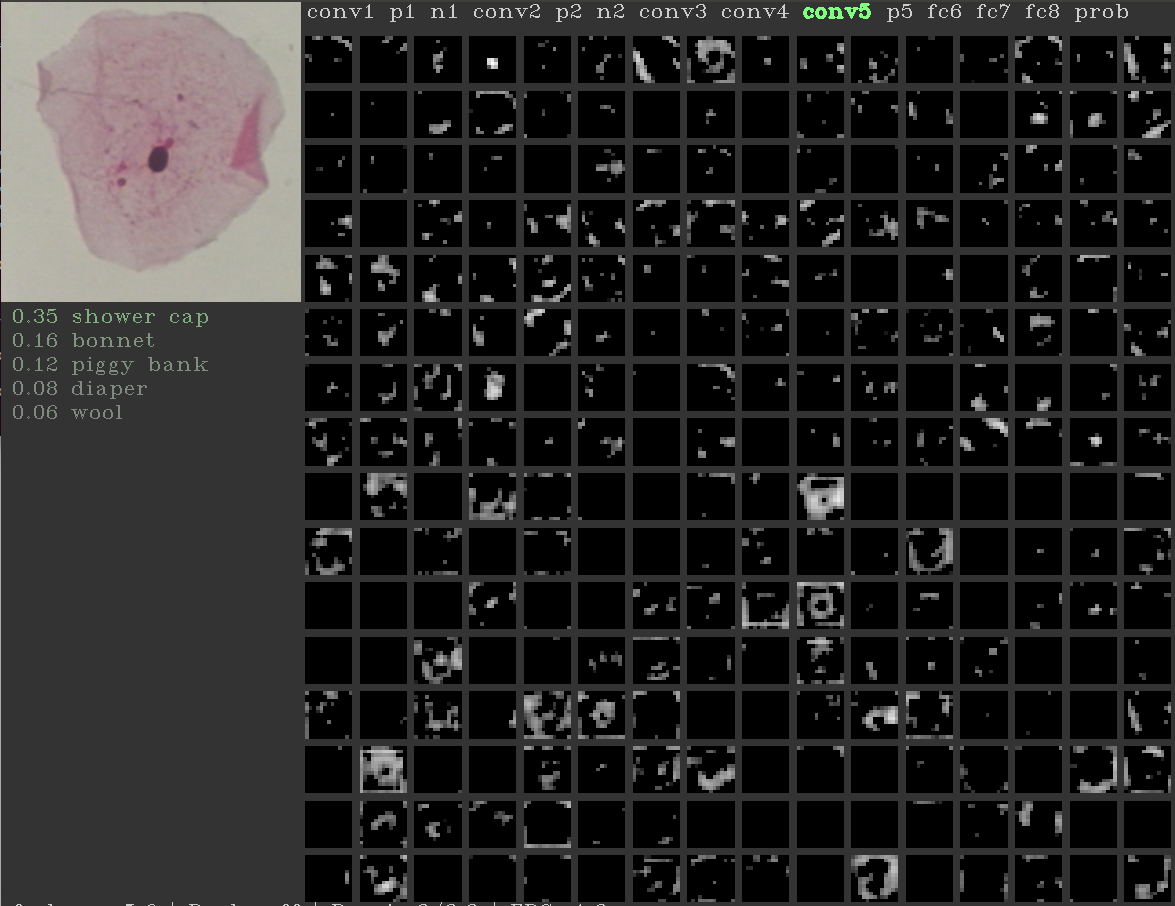

It is shown in literature that the lower level convolutional layers learn the low-level primitive features such as gradients, texture etc., and the deeper layers, learn the high-level data specific semantic features [21]. Considering the hypothesis that semantic features may not be important for cell classification, we explore for classification, the outputs from the filters learned by Alexnet [16] at last (conv5), intermediate (conv3) and first (conv1) convolutional layers followed by two fully connected layers which we retrain, one consisting of 256 neurons and the last layer consisting of number of neurons equal to number of classes. We refer to these new transfer-learning based networks in the rest of the paper as conv5T (Figure 4), conv3T (Figure 5) and conv1T (Figure 6).

Figure 4: conv5T: features from fifth convolutional layer of Alexnet.

Activation map from different convolutional layers of Alexnet for an example image are shown in Figure 10. It can be seen that the activation map from the first convolutional layer learns the prominant texture features from the images as opposed to the third and fifth convolutional layers. This observation supports the hypothesis that for cell images, as the depth of the network increases, the high-level features do not seem informative. This also supports our motivation to select Alexnet consisting of smaller number of layers. We provide the average training, validation and testing accuracies for the 7-class classification, over 5 random trials for different architectures in Figure 9. The constant increase in accuracies from conv5T to conv1T shows that the cell classification problem performs better with low-level features rather than those at the deeper levels. We believe this is an interesting and important insight, as typical deep learning approaches only consider the last layer features for classification.

Refer to caption

(a)

(b)

(c)

Figure 10: Activation maps: Left to Right: Conv1, Conv3 and Conv5 activation maps for Normal superficial cell images.